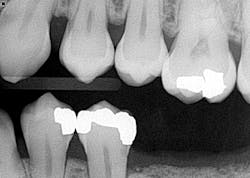

- Additional caries were noted on nos. 10, 11, 14, 26, 27, and 29—primarily facial/buccal caries (figures 3–8)

I put an entire treatment plan together that addressed the caries, perio, and replacement of the missing teeth, which included a consult with an oral surgeon. The patient clearly had needs, and I was not going to pick and choose what I would do because he was injured. A cavity is a cavity is a cavity. Everything was submitted to the workers’ comp company. If you have ever done one of these claims, you know that they are a pain in the you-know-what. The paperwork is endless, handwritten, and must be accompanied with all of the necessary documentation to “prove” all findings in order to support subsequent recommendations. More than six months of back and forth. Six months! Something of import to note is that not once did the patient call, inquire, or express concern as to how the case was progressing.